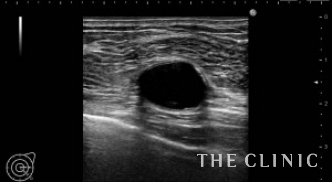

3年前に他院で脂肪注入による豊胸を受けられた方です。手術直後から痛みとしこりがあったとのことで、エコーにて右はオイルシストが1つ、左は混合性のしこりが2つあることを確認しました。

混合性のしこりは、ベイザーで崩して吸引除去します。オイルシストは穿刺吸引します。